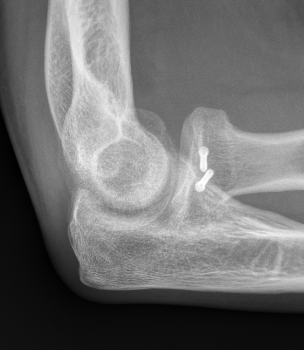

Overstuffing

| Lesser sigmoid notch | Symmetry of ulnohumeral joint |

|---|---|

|

Radial head shoulder articulate with lesser notch

Ensure no gapping of lateral ulnohumeral joint |

- cadaveric study

- increased medial ulno-humeral joint line gapping with overlengthening of 6 or 8 mm

- increased lateral ulno-humeral joint line gapping with overlengthening of 2 mm